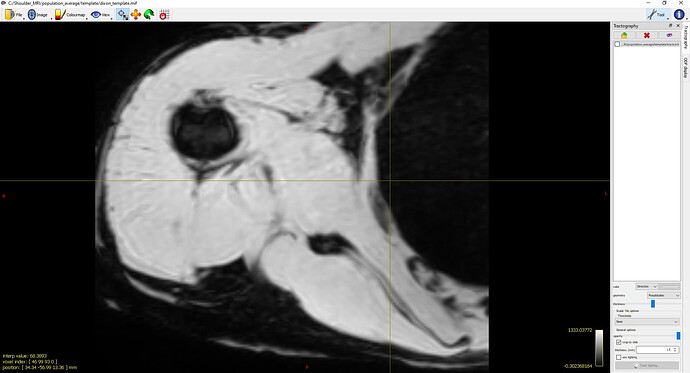

- Settings B:

population_template ../template/fod_inout/ ../template/fod_template.mif ../template/dixon_input/ ../template/dixon_template.mif -mask_dir ../template/mask_input/ -template_mask ../template/mask_template.mif -voxel_size 0.75 -nl_metric_radius 5 -nl_disp_smooth 0.75 (default 1.0 x voxel_size) -nl_update_smooth 1.5 (default 2.0 x voxel_size) -nl_niter 5,5,5,5,5,5,5,5,5,5,5,5,5,5,5,5(See Screenshot 3)

While the second setting slightly reduced the twisting, it was still noticeable. Interestingly, when I switched to SSD for non-linear registration, the twisting issue was resolved.